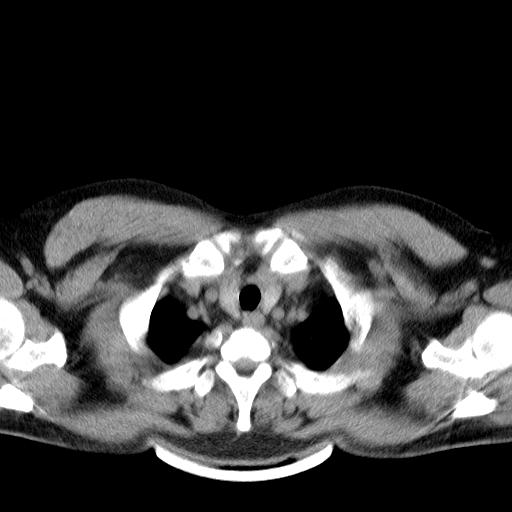

两肺散在大小不等小结节影,下野较多,纵隔淋巴结增大。考虑:1、慢性血播性肺结核;2、霉菌病?3转移瘤待排。

该病人肺内多发结节,右肺门似有肿大淋巴结,肺结节病也要考虑

双肺多发散在结节影,部分边界不清,延支气管分布;纵隔内多发小结节(淋巴结)影...

双肺散在多发类圆形结节灶,边缘较光滑,纵隔淋巴结肿大,考虑转移瘤

双肺及胸膜下见多发结节影,最大直径约0.4,内密度均匀,中纵隔腔静脉后见小淋巴结影。